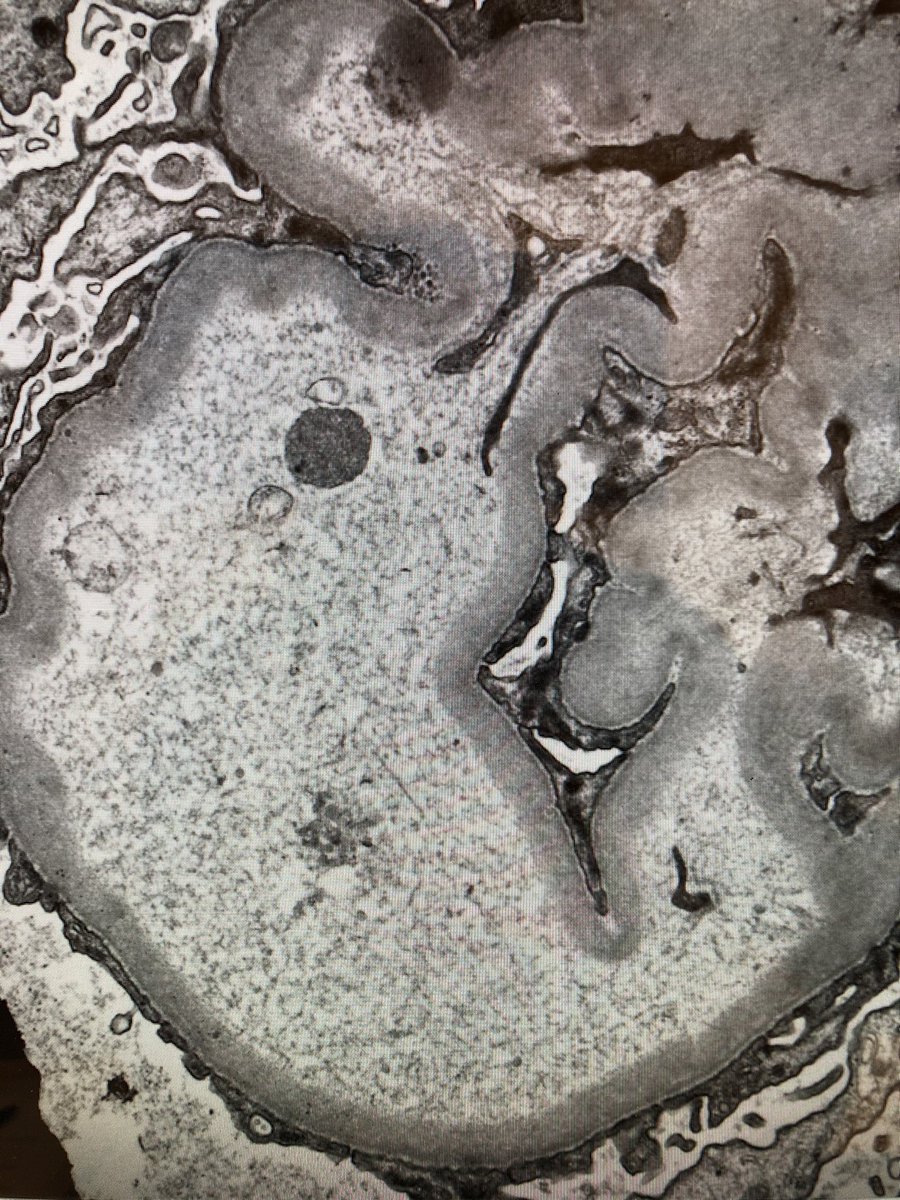

BK nephropathy blasts this unfortunate transplanted kidney. So many viral inclusions. Not hard to find viral particles by EM either. #renalpath #nephropath Jean Hou, MD

BK nephropathy blasts this unfortunate transplanted kidney. So many viral inclusions. Not hard to find viral particles by EM either. #renalpath #nephropath <a href="/JeanHouMD/">Jean Hou, MD</a>